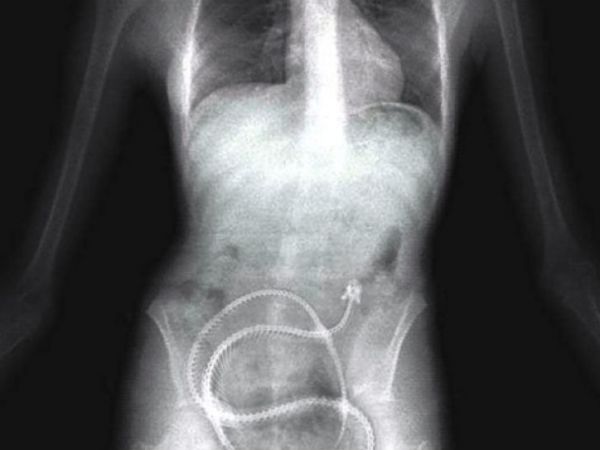

А так выглядит снимок человека, который проглотил немалое количество наркотиков, чтобы перевезти их контрабандой через границу.